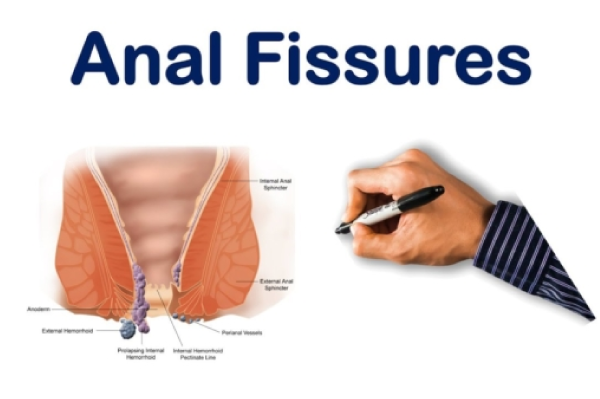

Anorectal Conditions

Anorectal refers to conditions related to the anus or rectum. These conditions are mainly caused due to some sort of overgrowth or abnormal growth of tissues in the anus and rectum region. While discussing these issues might be embarrassing, living with them can be painful. The common anorectal problems are:

Fissures

An anal fissure is a small tear in the skin lining on opening of anus. They are developed by hard or difficult bowel movements, causing severe pain or bleeding. Your doctor may recommend few changes in diet for soft stools, and topical anesthetics to reduce pain.

Causes of Fissure:

The most common cause of an anal fissure is injury to the skin at the anal opening due to a hard, dry bowel movement.Pregnant women may also develop a fissure during childbirth. They may be acute (recent onset) or chronic. Chronic fissures recur frequently or are present for a long time and are often associated with a small external lump called a skin tag or sentinel pile.